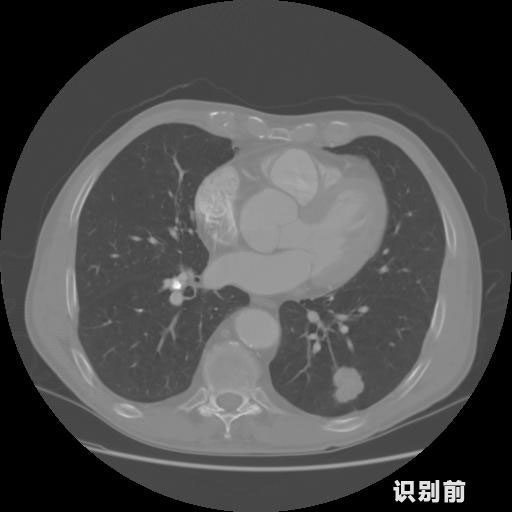

報告:

1.發(fā)現(xiàn)肺結(jié)節(jié)的可能性為95.56%---位于框指數(shù)位置:[331.70554 366.13406 365.21707 403.96234]